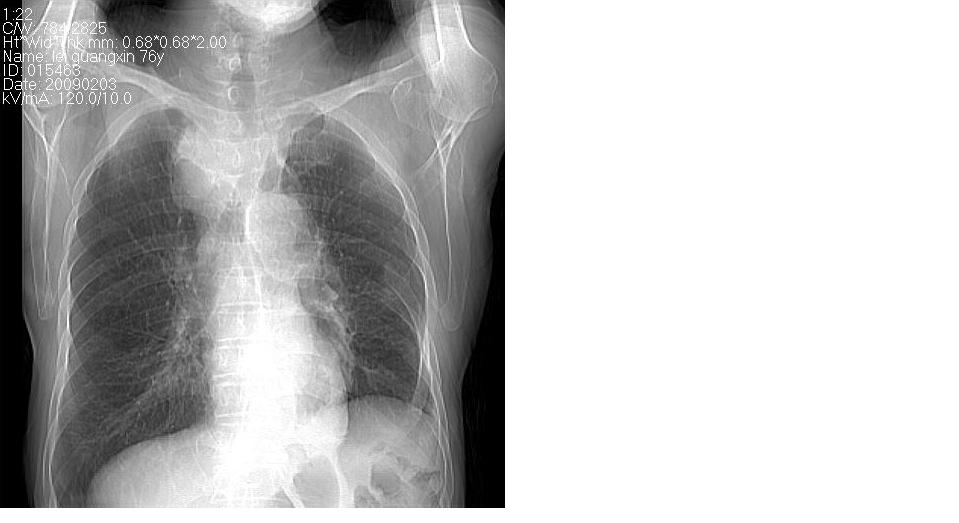

男 76岁,去年在外医院行食道癌手术,现胸闷,呼吸困难,肺窗有慢支肺气肿,无其它。

考虑----食管癌术后改变〔胃作食管重建术〕-------纵膈淋巴结转移

淋巴结转移,食道癌术后变胸腔胃。

纵隔淋巴结转移,纵隔术后改变、胸腔胃。

了解病史。支持纵隔淋巴结转移的诊断,但如果是上段食道癌术后就应考虑食道癌术后吻合口复发伴淋巴结转移。

上段食道癌术后,胸腔胃,术后吻合口复发伴淋巴结转移。